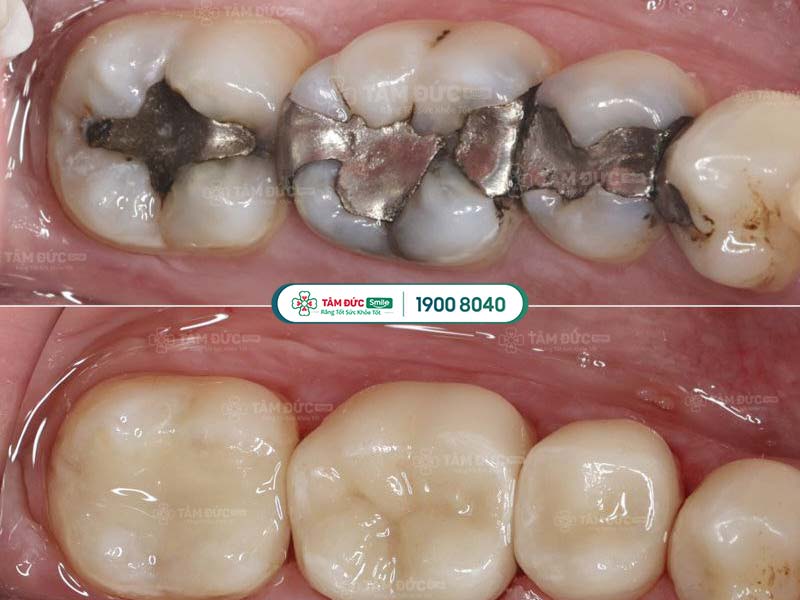

2.1. Amalgam

Amalgam (hoặc còn gọi là trám bạc) là vật liệu trám răng có màu bạc, xuất hiện từ lâu trên thị trường nha khoa. Thành phần chủ yếu của Amalgam bao gồm: Bạc, kẽm, đồng, thiếc và thủy ngân.

Loại vật liệu này rất bền, có độ chịu lực tốt và giá thành rẻ nhất trong tất cả các loại vật liệu trám răng. Tuy nhiên, do Amalgam có màu sắc khác biệt với màu răng, nên không được đánh giá cao về thẩm mỹ.

Răng được phục hình sau khi trám